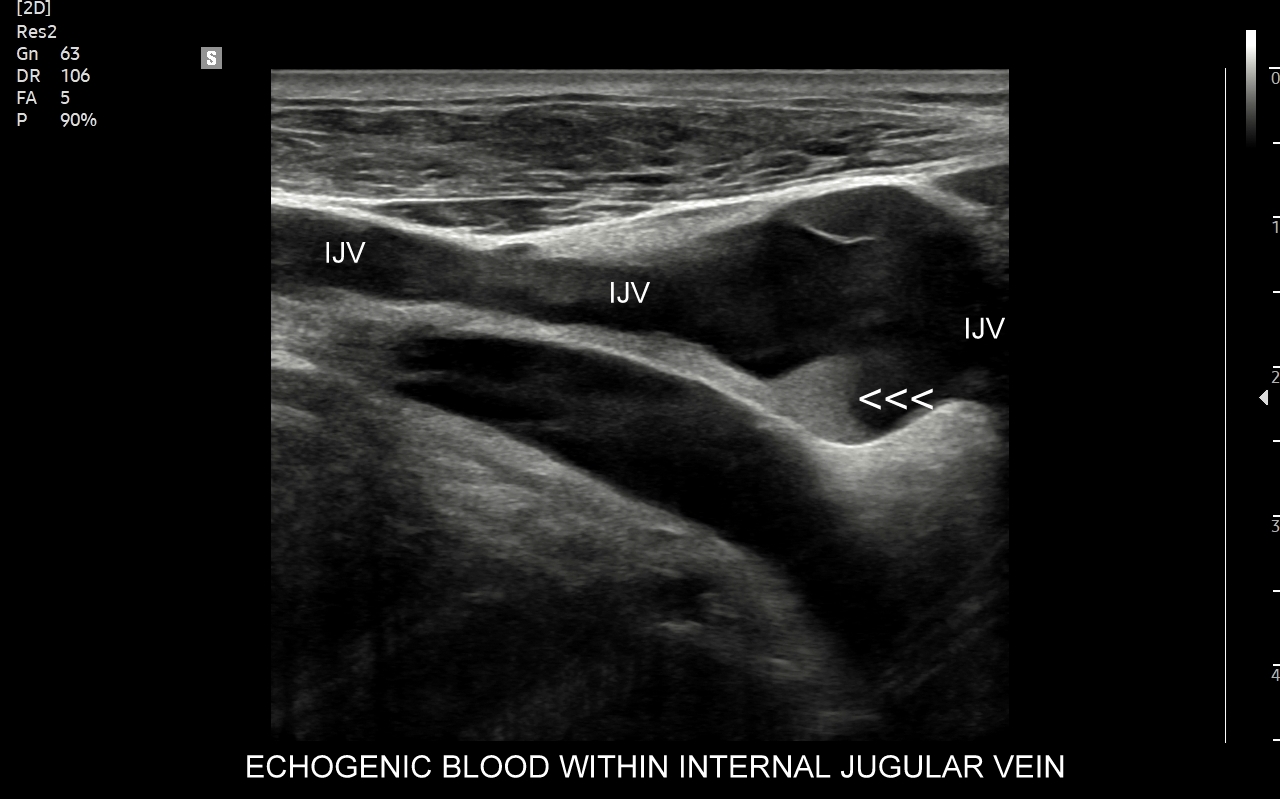

Czym jest zakrzepica żył? Zakrzepica żylna polega na powstaniu skrzepu wewnątrz naczynia żylnego i wtórnym rozwoju stanu zapalnego w okolicy naczynia. Choroba dotyczyć może układu powierzchownego żył lub żylaków, a w tym wypadku nie jest zwykle stanem niebezpiecznym; a także układu głębokiego żył, co z kolei jest stanem potencjalnie zagrażającym życiu, gdyż może sprowokować zatorowość płucną. Zakrzepica żył głębokich (ang. deep venous thrombosis DVT) częściej występuje w obrębie żył kończyn dolnych, następnie w obrębie żył biodrowych, rzadziej w żyle podobojczykowej i żyłach głębokich kończyny górnej. Przyczyny zakrzepicy żylnej są różnorodne i obejmują m. in. długie podróże, długotrwałe unieruchomienie, operacje ortopedyczne, chirurgiczne i szczękowe, urazy tkanek miękkich oraz złamania kości, genetycznie uwarunkowane trombofilie, nowotwory złośliwe, odwodnienie, infekcje miejscowe i ogólnoustrojowe. W przypadku zakrzepicy żyły podobojczykowej klasyczną jej przyczyną jest ucisk; w swojej praktyce klinicznej dr Szczepański spotkał się z zakrzepicą podobojczykową wywołaną m. in. przez ciężki plecak, wyciskanie sztangi na siłowni, czy przez uprawianie wspinaczki skałkowej. W warunkach szpitalnych zakrzepica żyły podobojczykowej lub żyły szyjnej wewnętrznej może pojawić się w wyniku zakładania cewników dożylnych. Sprawne wykrycie zakrzepicy w badaniu USG, a następnie wdrożenie odpowiedniej terapii uchronić może pacjenta przed powikłaniami ostrymi (np. zator płucny), jak i opóźnionymi (np. zespół pozakrzepowy).

USG Doppler żył szyjnych i kończyn górnych

Badanie USG Doppler żył szyjnych, podobojczykowych i żył kończyn górnych najczęściej wykonywane jest z powodu spontanicznych zakrzepów pojawiających się w przebiegu takich schorzeń jak odwodnienie, nadużycie napojów „energetycznych”, zespoły uciskowe, zespół górnego otworu klatki piersiowej, choroby nowotworowe i mieloproliferacyjne, trombofilia, czy jatrogenne powikłania cewnikowania żył. U osób zdrowych, tj. bez obciążeń trombofilnych, zakrzepica w zakresie żył obręczy kończyny górnej zwykle występuje jako powikłanie ucisku, np. przez mięśnie u osób podnoszących ciężary na siłowni albo przez ramiączka ciężkiego plecaka podczas wędrówek krajoznawczych. Objawami zakrzepicy żyły ramiennej, pachowej, podobojczykowej, czy żylnego pnia ramienno-głowowego zwykle są uczucie dyskomfortu w kończynie górnej, ból, ograniczenie ruchomości, zasinienie i obrzęk kończyny górnej, pojawienie się poszerzonych naczynek na ścianie klatki piersiowej.